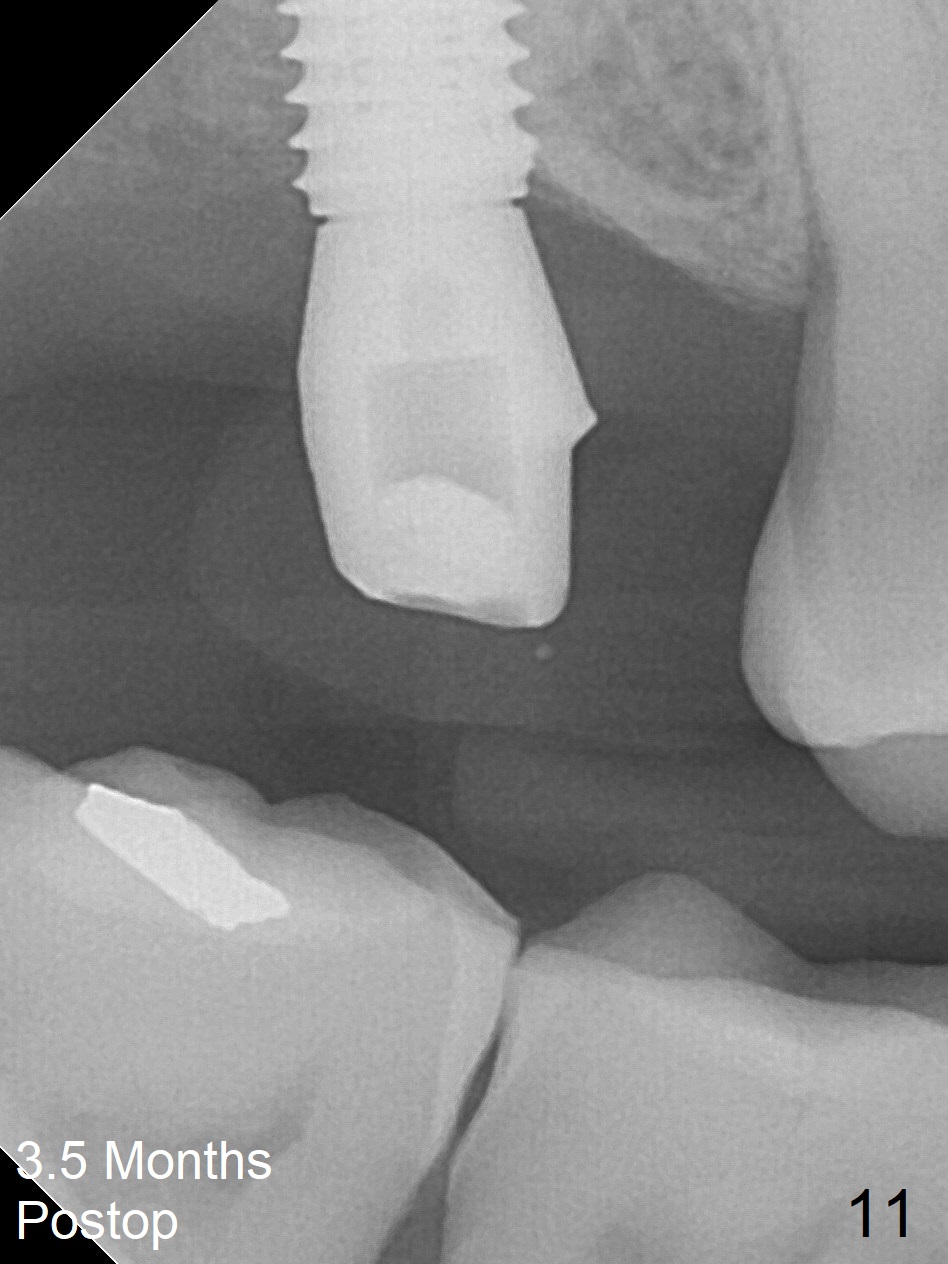

After extraction of the 3rd molar with mesial periodontal defect, osteotomy for 2nd molar implant is initiated in the mesial slope of the 3rd molar socket (Fig.1 red dashed line). When osteotomy is finished with IS drills and sinus lift with Magic Sinus Lifter (S-reamer with 11 mm stopper being short), a 4x10 mm dummy implant is placed with ~ 4 implant thread exposure (Fig.3). Following use of Lindamann bur to move osteotomy mesial and larger drill, a 4.5x10 mm implant is placed with 5-7 implant threads exposed distally (Fig.4,7 (~ 50 Ncm)). The bucco(B)-palatal(P) extent of the implant thread exposure is larger (Fig.5) than that associated with the 4 mm dummy implant (data not shown). The exposed implant surface is covered with Vera Graft (Fig.7*), Collagen plug and an immediate provisional after adjustment of abutment height (Fig.6,7). The bone density distal to the implant is low 3 months postop (Fig.8,9 CBCT) and 3.5 months postop (Fig.10,11). The permanent crown is cemented nearly 4 months postop. The distal cortical bone contacts the implant (Fig.12 ^), while the mesial bone increases in density (*) 2 years postop.